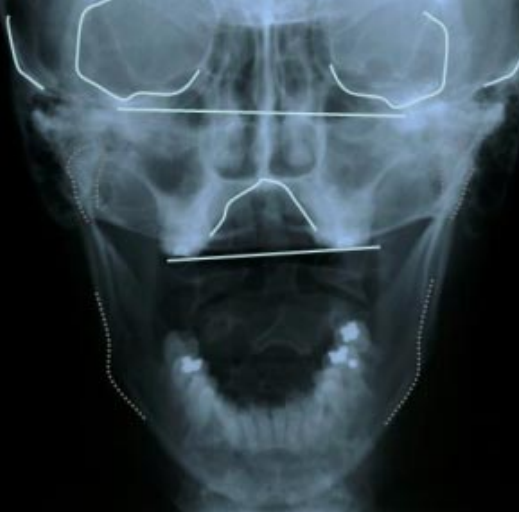

Side-Bending Rotation is when two key bones at the base of your skull — the sphenoid and occipital bones — do two things at once:

According to cranial structure research, Side-Bending Rotation is the most common distortion found in combination with other imbalances. Specifically, it usually comes paired with something called a "vertical strain" — where your skull is also compressed or elongated vertically.

Eyes are at different heights — one higher, one lower. Twist plus tilt, simultaneously.

Twist plus tilt — a layered, compound distortion. "Everything feels crooked, not just one thing."